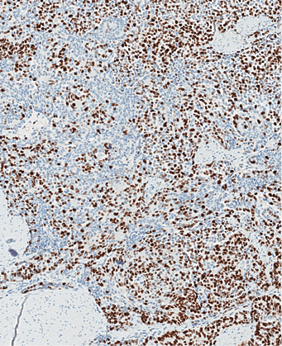

Imunohistocheminio profiliavimo metu nustatyta stipri difuzinė PanCK reakcija visuose komponentuose (3 pav.) ir menka, tačiau definityvi MUC2 žarninio tipo mucinų produkcija (4 pav.) kartu su tipiška KRAS geno 12-o kodono mutacija 2-ame egzone leistų klasifikuoti naviką kaip aukšto laipsnio (blogai diferencijuotą) adenokarcinomą. Ieškant biologinio pagrindo neįprastai naviko morfologijai paaiškinti atliktos papildomos imunohistocheminės reakcijos: Hep-Par1 (neigiama), INI1 (praradimo nėra), BRAF (neigiamas, tikėtina, nemutuotas), PMS2 ir MSH6 (reakcija išlikusi, nėra mikrosatelitų nestabilumo audinyje požymių), visose naviko ląstelių populiacijose patvirtintas jau biopsijoje identifikuotas difuzinis neuroendokrininis fenotipas (100 % Synaptophysin ir 95 % Chromogranin A ekspresija (5 pav.)). Ki67 proliferacinis aktyvumas buvo heterogeniškas ir rabdoidinės išvaizdos komponente siekė 90 proc., o likusiuose buvo perpus žemesnis (6 pav.).

5 pav. Stipri difuzinė neuroendokrininių žymenų Synaptophysin (1)ir Chromogranin A (2) ekspresija visuose naviko komponentuose